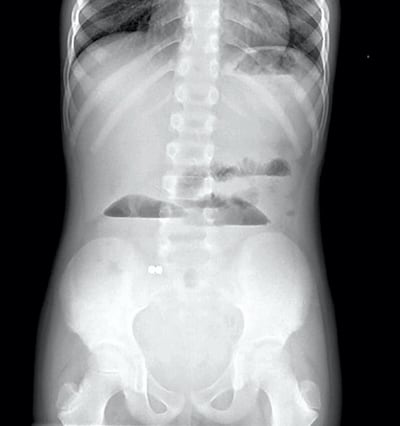

Coins are the most common item ingested, followed by small batteries and magnets.

The small, disc-shaped varieties are considered the most dangerous by experts as heat generated by their powerful electric charge can cause serious burns.

He also warned that repeated X-rays on children risked exposing them to needless doses of radiation.